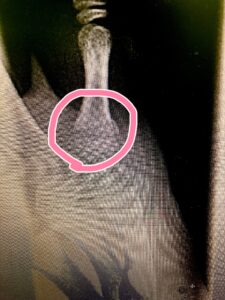

一目見て、骨折とわかるほどの腫れ😩

とりあえずテーピングで応急処置。

後日、固定してレントゲン🩻。

ばっちり折れてました😅

IMG_6958